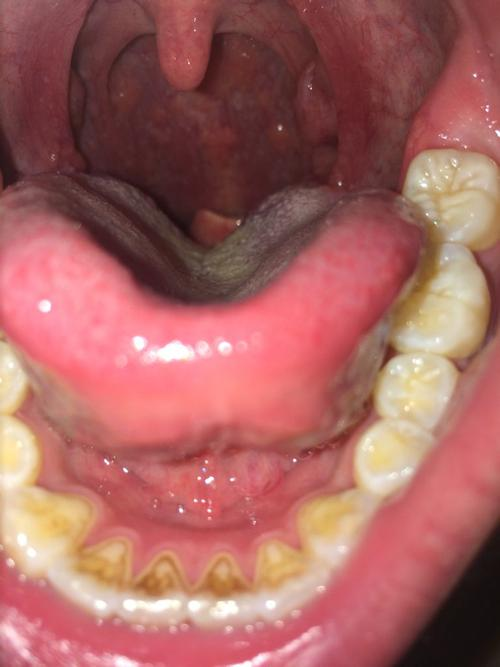

舌头根部出现很多红疙瘩可能是正常生理结构,也可能是疾病导致,具体原因如下正常生理结构舌头根部靠近喉咙的位置分布着轮廓乳头,这是人体正常的解剖结构,表现为凸起的红疙瘩状组织,每个人都存在,通常无症状,无需特殊处理疾病因素慢性咽炎咽喉黏膜长期受炎症刺激,可能导致舌根处黏膜肿胀发红。

舌头根部长很多小肉色泡泡且不痛,可能是正常生理结构,也可能是疾病导致,需进一步检查和诊断,具体如下可能是正常的生理结构轮廓乳头位于舌头根部靠近喉咙处,呈人字形排列,是正常口腔结构,可能看起来像小肉色泡泡舌扁桃体在舌根后部,是免疫系统的一部分,也可能呈现类似形态此外,舌头上的味蕾。